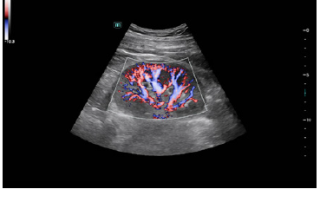

Mindray Ultrasound Consona N9